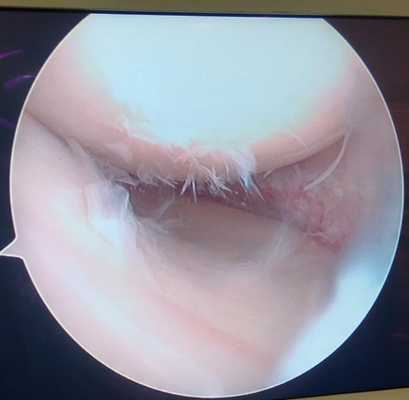

Дегенеративный комбинированный разрыв тела и заднего рога внутреннего мениска коленного сустава.

Продольный разрыв заднего рога наружного мениска, сопровождающийся его гипермобильностью. При таком разрыве мениск может значительно смещаться внутрь сустава создавая ощущение механического блока, инородного тела, нестабильности в суставе, заклинивания, щелчков.